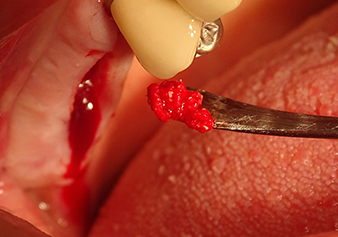

Following an intermediate check (Fig. 4) a further preparation step was performed (Fig. 5). Afterwards, the hydraulic Z35P instrument was used to lift the membrane to the desired position (Fig. 6 and 7). This was followed by further piezosurgical preparation of the implant bed, concluded with a rotary bur and shoulder milling cutter up to the implant diameter of 4.8 mm. Before the implant was inserted, the augmentation material (particle size approx. 0.8-1.6 mm) was introduced underneath the Schneiderian membrane (Fig. 8).

Implantation and prosthetic restoration